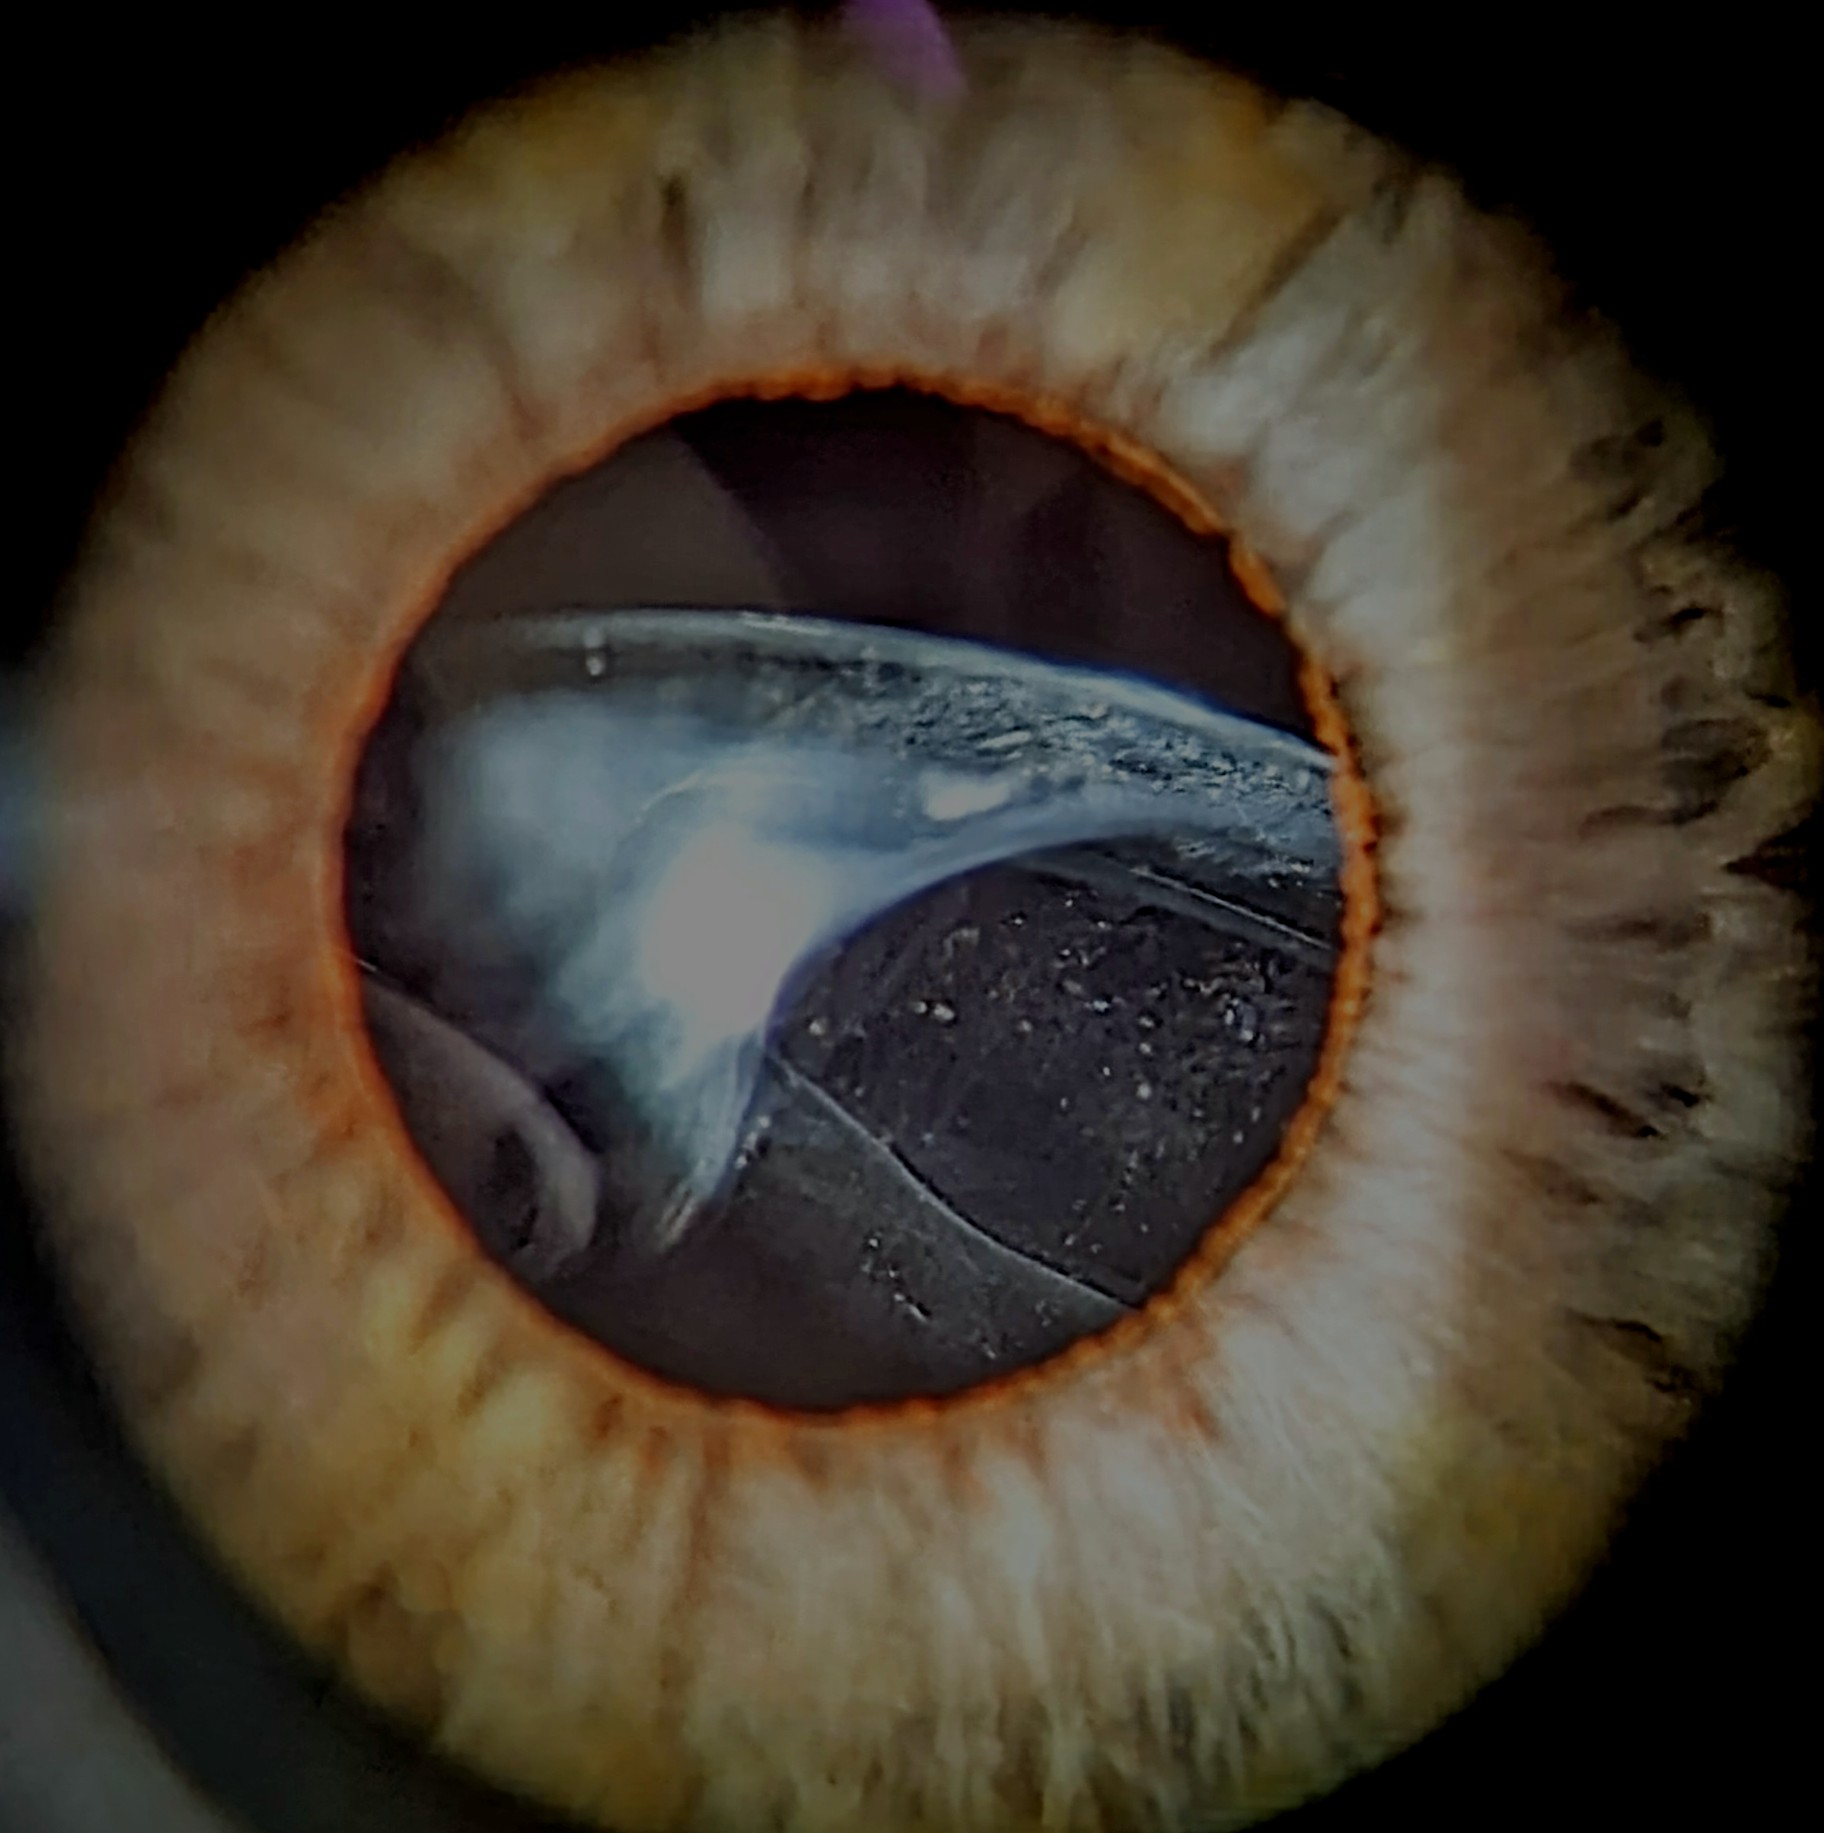

Voici quelques exemples de photos des années passées :